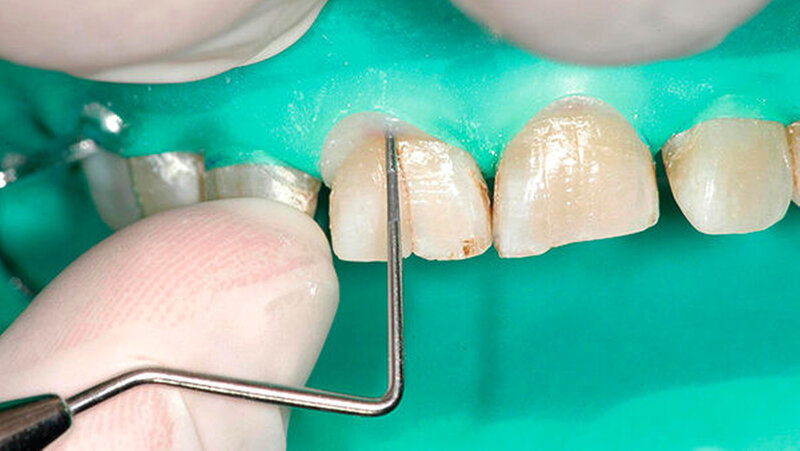

Bei der Vorstellung in der Poliklinik zeigte sich klinisch eine Schmelzfraktur auf der bukkalen Fläche des Zahns 11 (Abbildung 1). Die Messung der Taschensondierungstiefe (TST) ergab an dieser Stelle lokal begrenzt einen Wert von 7 mm (Abbildung 2). An allen übrigen Messpunkten lag eine physiologische TST von 3 mm vor.

Sowohl klinisch als auch röntgenologisch zeigte sich nach der Behandlung ein erfolgreich replantierter Zahn (Abbildung 8). Bereits nach dreimonatiger Einheilungsphase reduzierte sich die Taschensondierungstiefe von 7 mm auf 3 mm (Abbildung 9).